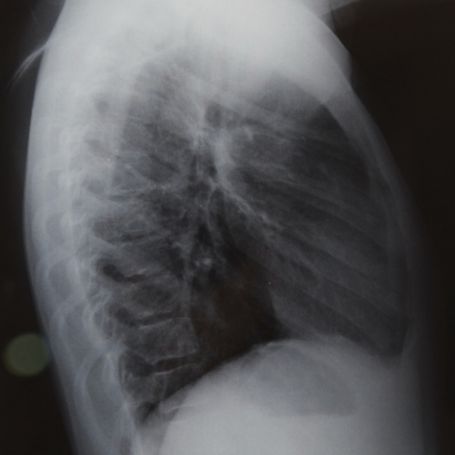

The X-Ray Right Shoulder Outlet View is a specialized imaging test that captures detailed images of the shoulder joint, including the acromion, clavicle, humeral head, and surrounding structures. It helps doctors accurately detect shoulder impingement, fractures, or rotator cuff injuries. At Diagnopein, Karad, we use advanced digital X-ray equipment to provide precise and clear images, ensuring accurate diagnostic reports for effective treatment planning.

This specific X-ray view is vital because it visualizes the shoulder joint in a way that standard X-rays may not, showing the alignment of bones and soft tissues from a unique angle. It’s an important tool for orthopedic surgeons, radiologists, and sports medicine practitioners.

The Right Shoulder Outlet View X-Ray provides a clear image of the shoulder’s bony outlet, allowing doctors to identify structural abnormalities or injuries that may not be visible on other views. It is especially helpful for diagnosing: